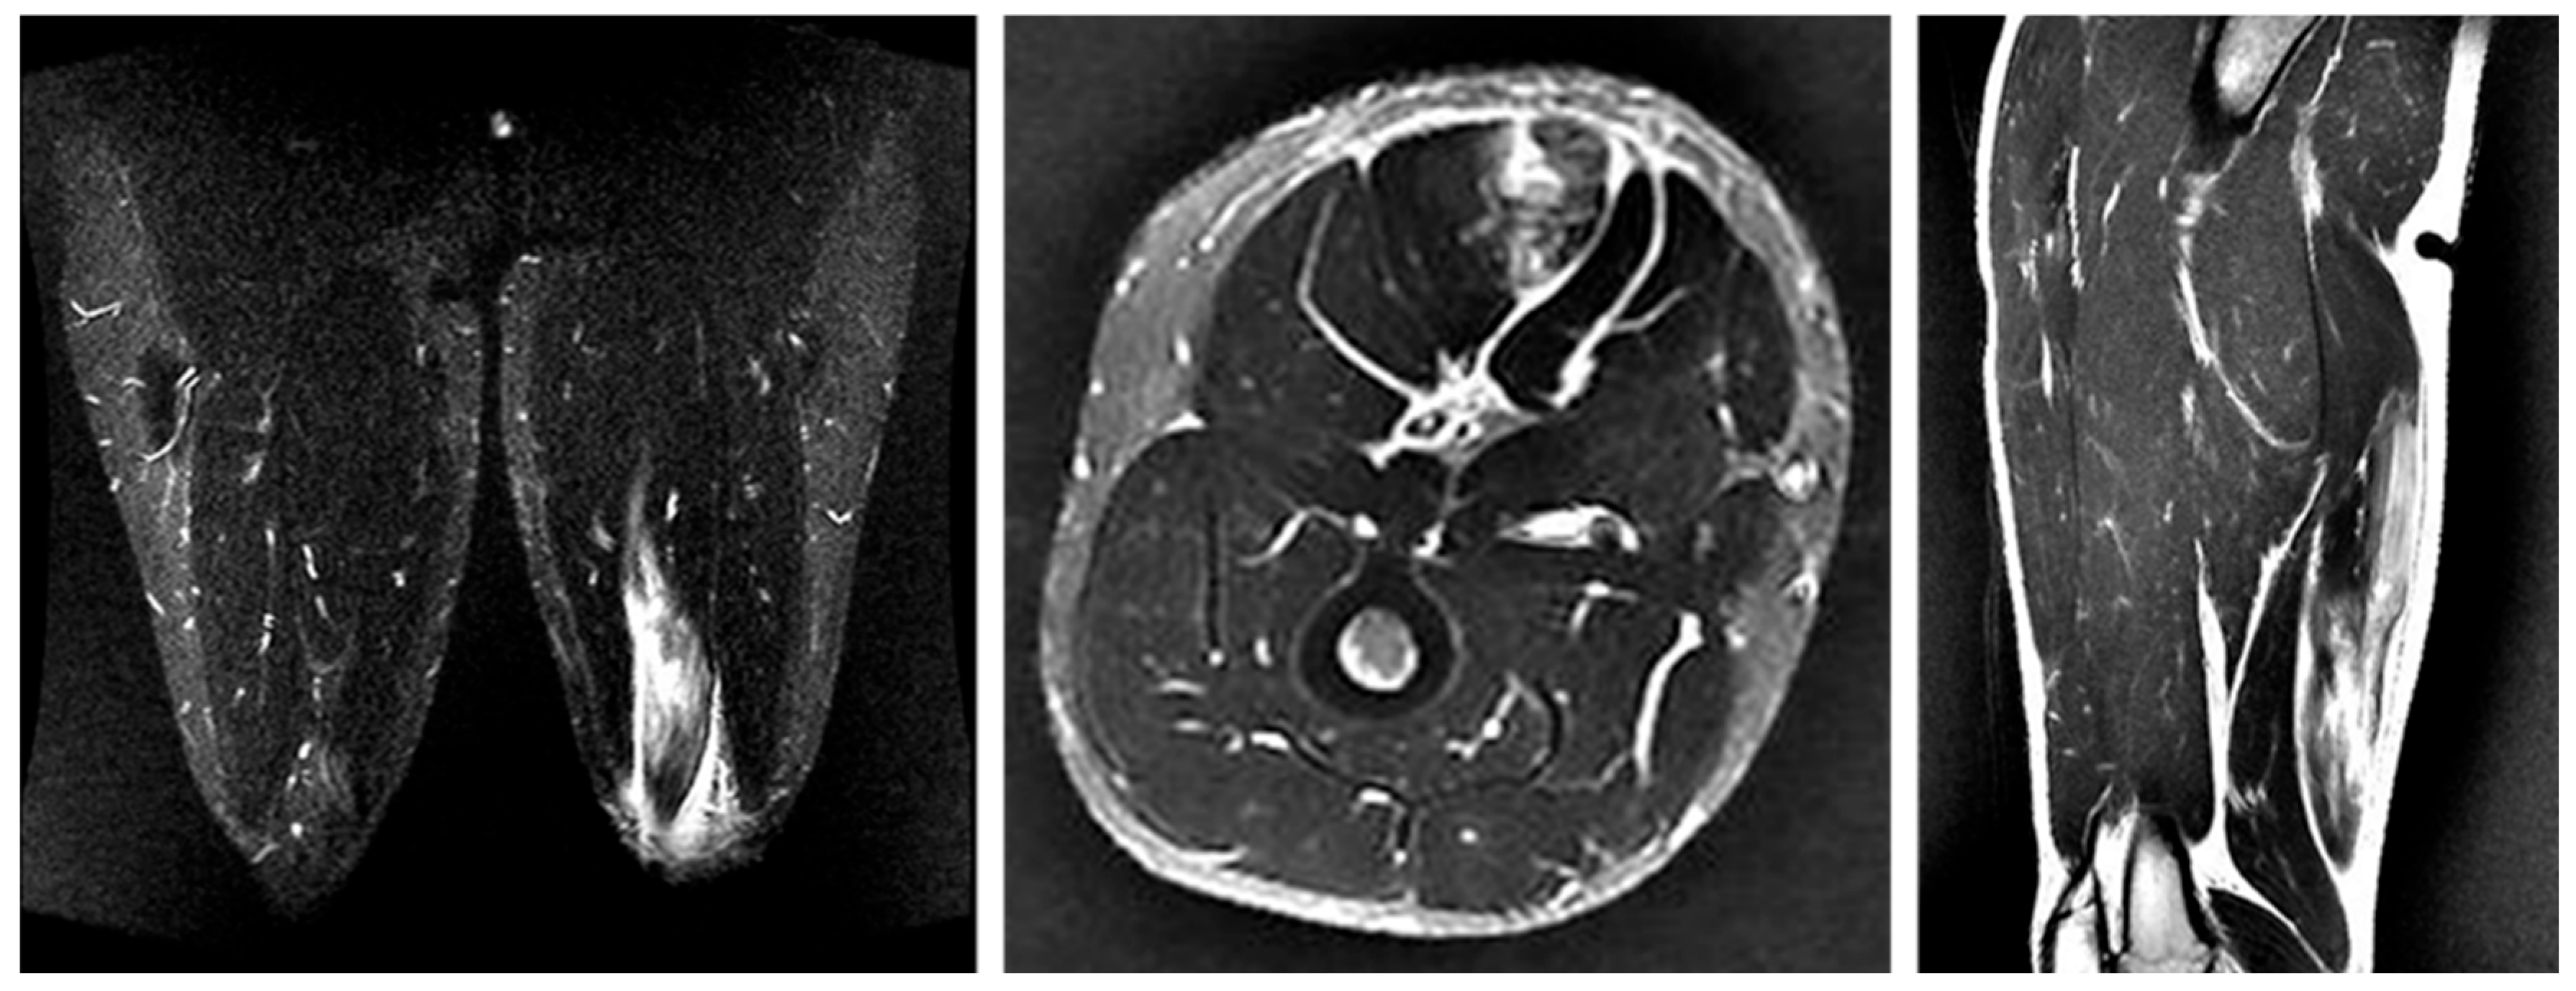

3.4.1. Case 1—Type I/Zone A (Conjoint Tendon Detachment), Grade 2

A 20-year-old lock (FW) stepped to evade an opponent while running with the ball and experienced a sharp tearing sensation in the posterior thigh near the origin. He returned to competition after 20 weeks (Figure 4).

Figure 4. Case 1 MRI images: Conjoint tendon detachment, Type I. (A) (Coronal image): The CT (conjoint tendon) is damaged near the ischial tuberosity, with the haematoma extending to the MTJ. However, the retraction of the ruptured tendon is not severe. (B) (Axial image): prone position, The CT is detached from the ischial tuberosity in zone A. The SM tendon is normal. (C) (Sagittal image): The injury is located proximally to the CT, with the haematoma extending distally into the inter-muscular space.